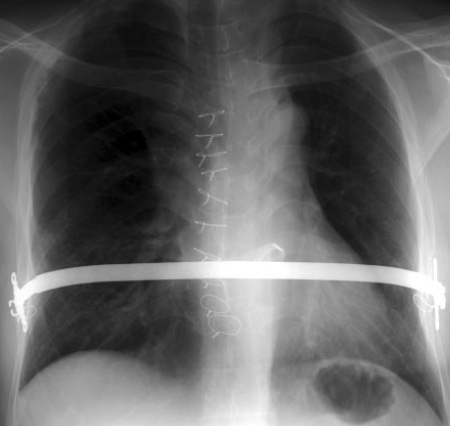

- Pectus Excavatum (Chir si index de Haller > 3.4)

- Pectus Carinatum